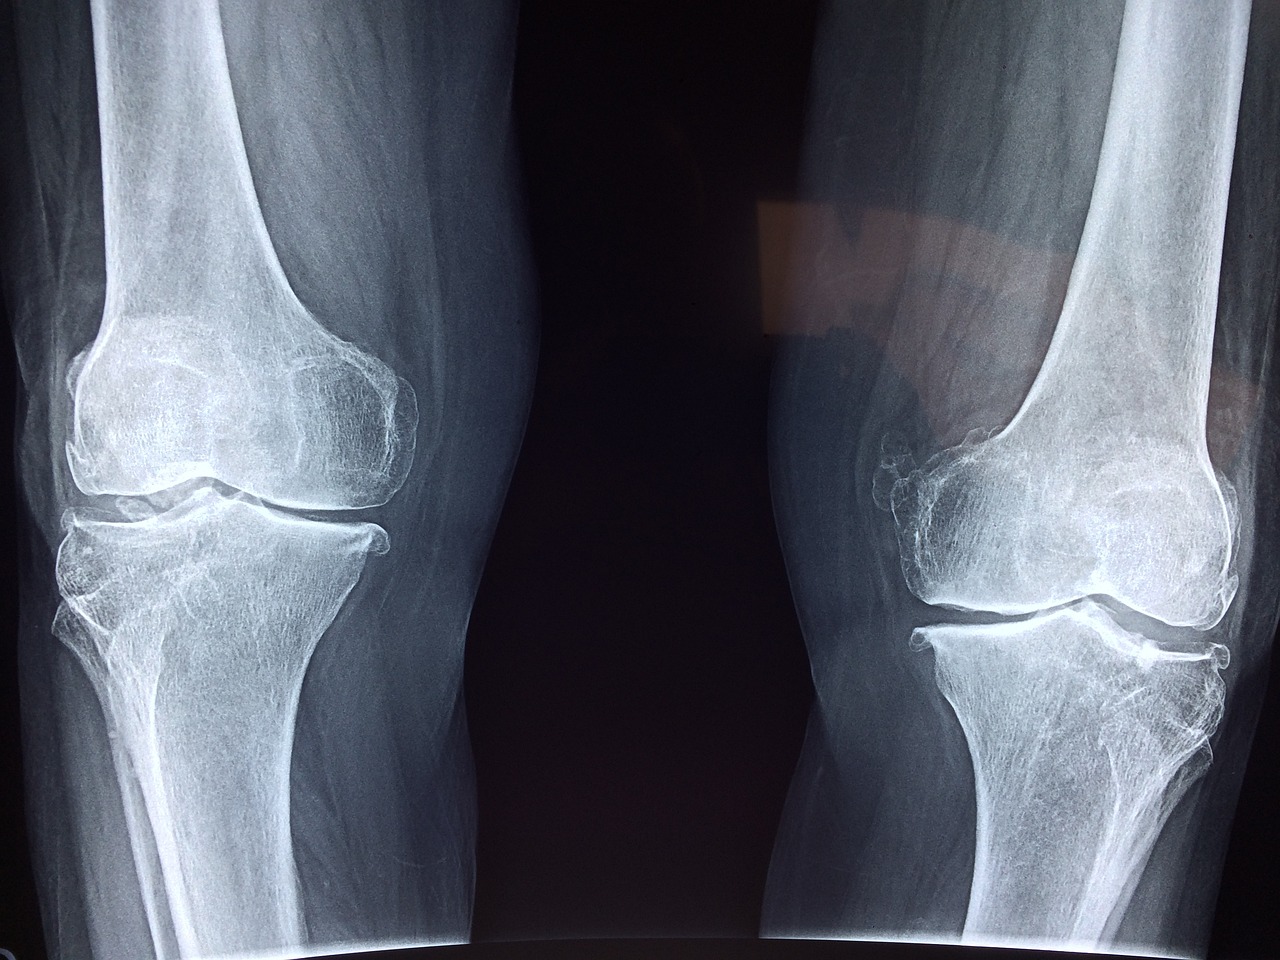

40-50대가 되면 뼈 밀도가 점차 줄어들기 시작해요. 특히 여성은 갱년기로 인해 골다공증 위험이 커질 수 있죠. 칼슘은 뼈를 튼튼하게 유지하는 데 꼭 필요해요.